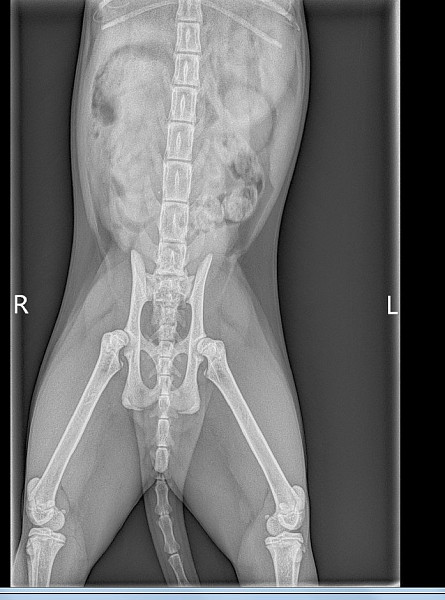

Перелом бедра у кошки

Перелом бедра у кошки 139 фотографий